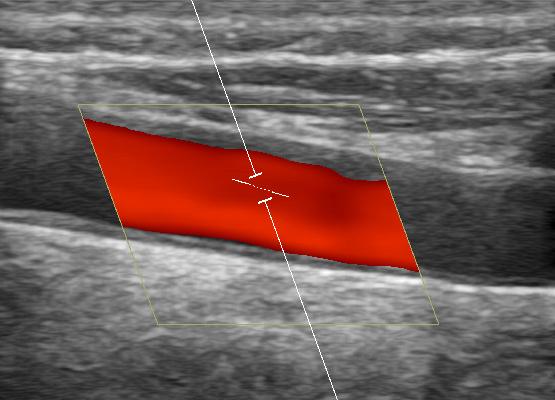

Gefäßdarstellung mittels Ultraschall

Bei der Doppler-Duplex-Sonographie der Halsgefäße wird untersucht, ob Verkalkungen (Plaques) vorliegen, und ob es dadurch zu Verengungen (Stenosen) kommt.

Neben dem Aussehen der Plaques wird die lokale Flussgeschwindigkeit des Blutes beurteilt: Je schneller die Flussgeschwindigkeit, desto hochgradiger die Stenose.